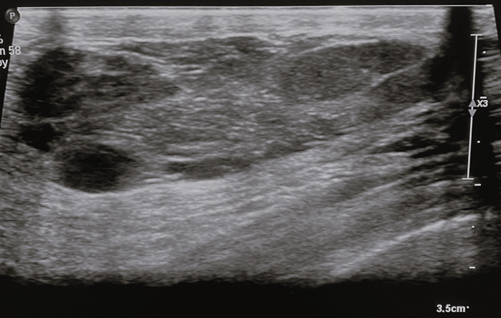

On ultrasound, the appearance of MH differs widely owing to the marked variability in the fatty and fibrous tissue constituents. They generally appear as solid, well-circumscribed, oval formations with heterogeneous echogenicity [24], aligned parallel to the skin plane (Figure 3). The lesion typically lacks hypervascularization on colour Doppler imaging and shows an echogenic or echolucent halo with posterior strengthening [2]. Incomplete pseudocapsule and tiny size with minimal fat content might make diagnosis challenging [8].

Figure 3. Breast ultrasound – breast ultrasound shows a tissue formation with the long axis parallel to the cutaneous plane, well-circumscribed, heterogeneous, with hypoechoic with hyperechoic trabeculae and posterior acoustic enhancement. Image credits: El Yousfi Z, El Mansoury FZ, El Bakkari A, Omor Y, Latib R. Breast hamartoma with synchronous contralateral breast cancer: a case report. Cureus 2024; 16(8): e66534. DOI: 10.7759/cureus.66534. Reused under the terms of the Creative Commons Attribution License CC-BY 4.0. (https://creativecommons.org/licenses/by/4.0/deed.en).